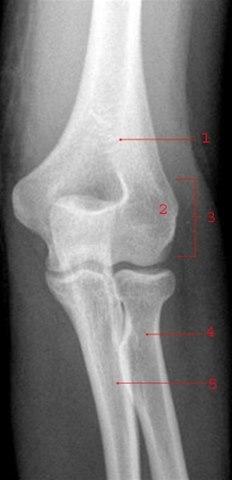

Underarmen består av to bein: spolebeinet (radius) på tommelsiden og albuebeinet (ulna) på lillefingersiden. Disse to beina danner ledd med overarmsbeinet (humerus) i albuen og med håndrotsbeina i håndleddet. Beina holdes fast sammen av bindevev. Se røntgenbilder av et normalt albueledd forfra og fra siden nedenfor:

Det skiveformede radiushodet (caput radii) danner ledd med capitellum på humerus. Brudd i radiushodet kan inndeles i flere undertyper (Mason type I til IV) og er det hyppigste (30 prosent) albuebruddet blant voksne.